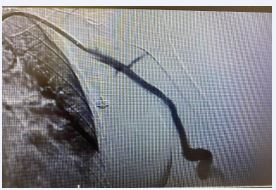

The Wrapsody stent was implanted through a basilic vein puncture, then a guidewire placement past the arterial stent femoral artery loop with a clothesline construction. Final arteriography demonstrated stent patency with excellent outflow (Figures 5 and 6).

Figure 5 Postoperative image showing covered self-expandable Merit Wrapsody 8x125mm Merit Wrapsody.